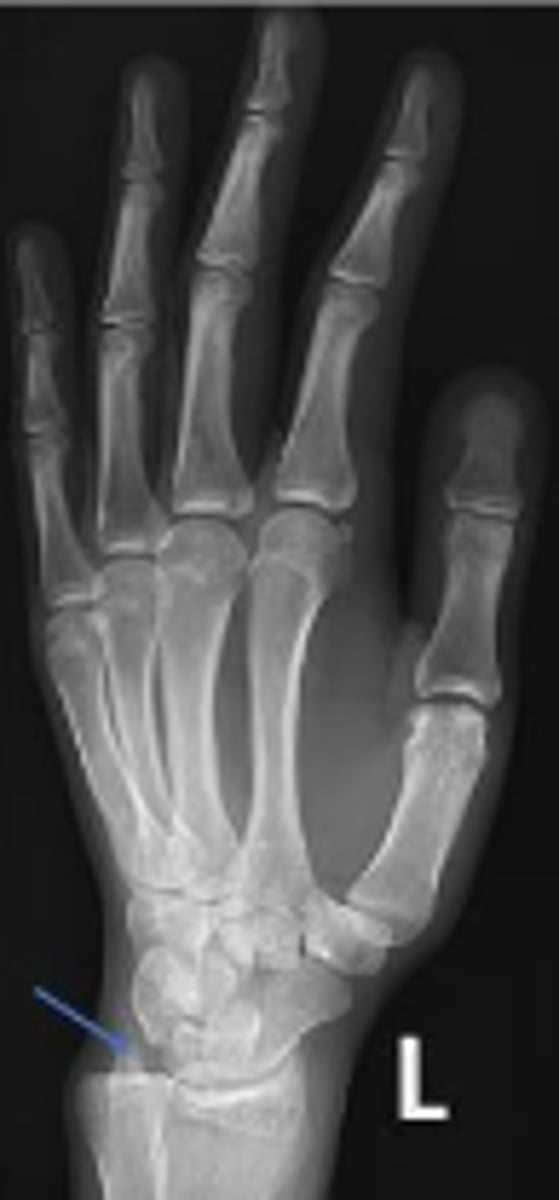

Left lateral wrist

What is the name of the radiographic view?